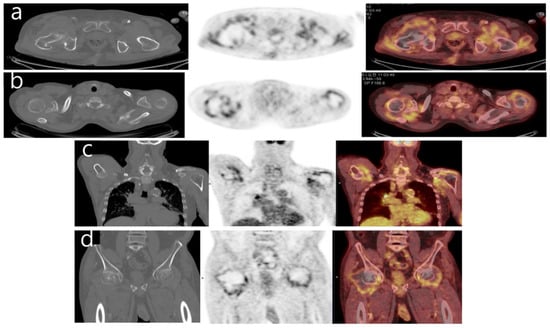

Visualization of Dialysis-Related Amyloid Arthropathy on 18F-FDG PET-CT Scan

Cheon, M.; Yoo, J. Visualization of Dialysis-Related Amyloid Arthropathy on 18F-FDG PET-CT Scan. Diagnostics 2022, 12, 113. https://doi.org/10.3390/diagnostics12010113